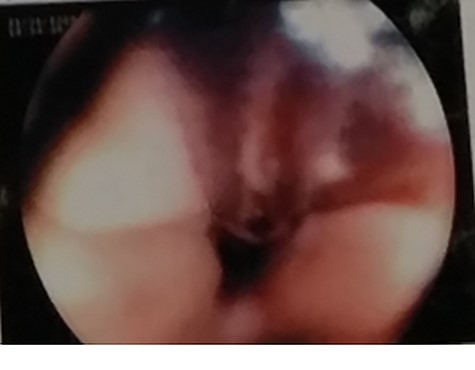

Ultrasound of abdomen and pelvis was normal. Upper gastrointestinal tract (UGI) endoscopy was done immediately, which revealed ulceration with a blood clot at 25 cm of the esophagus (Fig. 1).

UGI endoscopy, clot with underlying ulceration in the esophagus.